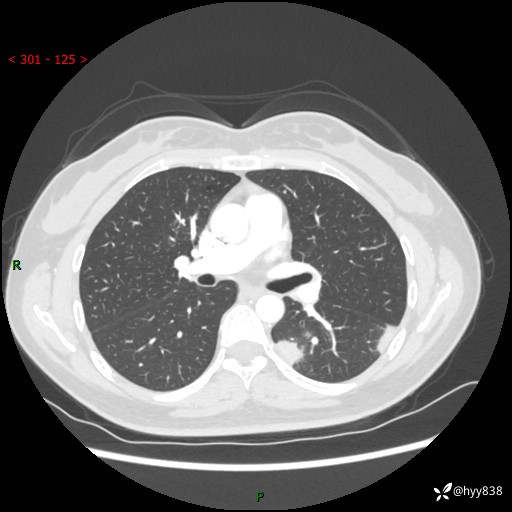

【患者信息】:36岁/女

【主诉】:左侧下胸部阵发性疼痛2周,乏力1周

【现病史及既往史】:患者自诉2周前饮酒后出现左侧下胸部阵发性疼痛,不随呼吸改变,无咳嗽咳痰、头晕头痛、咳血、呼吸困难等不适,于当地第一人民医院查胸部CT提示肺部感染,随后前往我院门诊给予抗感染(左氧氟沙星)治疗1周,自诉胸痛较前好转,感乏力、头晕,偶尔干咳,无咳痰,无发热、畏寒、胸闷、咯血、四肢酸痛、腹泻、腹痛等不适,门诊复查胸部CT提示:左肺下叶感染,病灶较前增加增大,遂以“肺部感染”收入我科。 起病以来,患者精神、饮食、睡眠可,大小便正常,体力体重无明显变化。

【检查】:胸部CT增强(外院平扫)